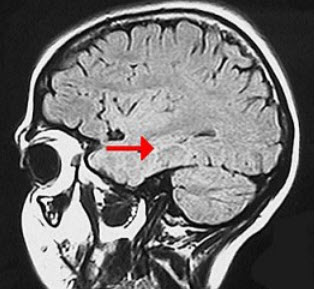

如图箭头所示为大脑哪个部位( )

A:壳核

B:丘脑

C:尾状核

D:岛叶

E:海马